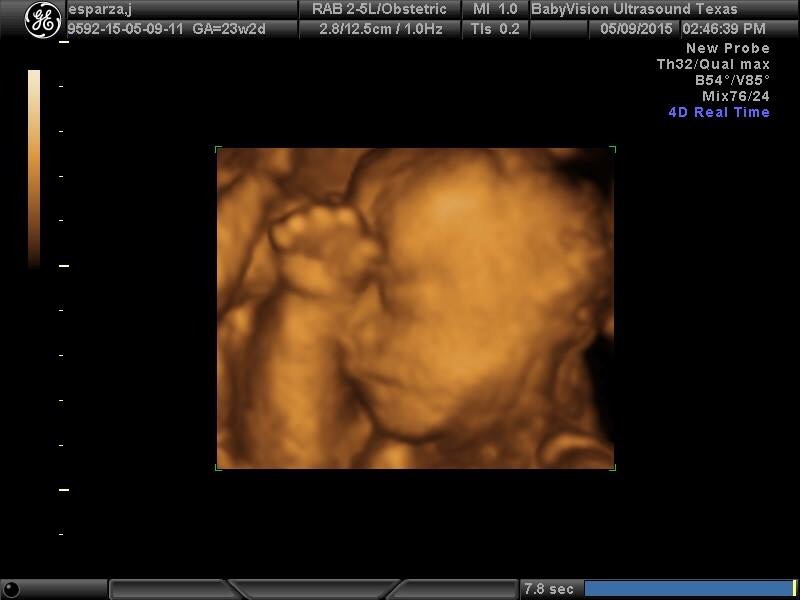

• My 20 week ultrasound pictures were blurry and dark so I scheduled a 3d/4d ultrasound to have nicer 2nd tri photos. I think it was well worth it. These were at 23 weeks and I'll be returning around 30 weeks to see if baby will look like more like his dad or me lol. I paid $95.